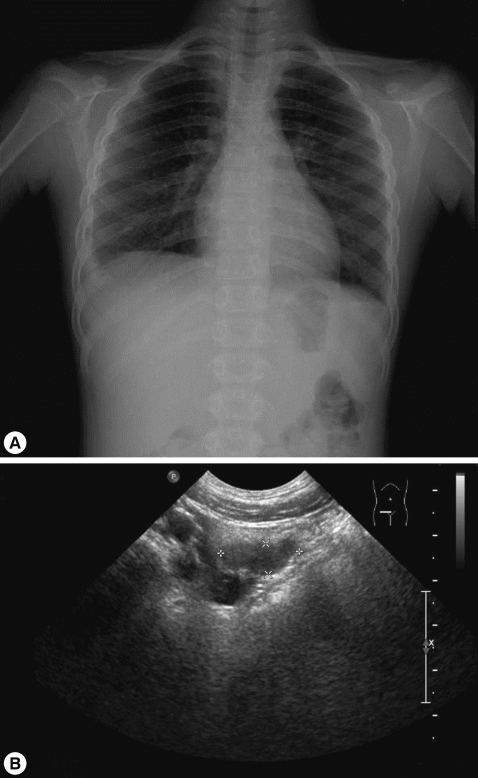

On admission, her vital signs were as follows: body temperature, 37.8℃; heart rate, 90/min; respiratory rate, 24/min; and blood pressure, 100/70 mmHg. On examination, she looked very ill and her breathing sounds were decreased on both sides of the lower chest. Moderate tenderness was detected in the right flank and the right inguinal area. A chest radiograph indicated pleural effusion (Fig. 1), and abdominal sonography revealed an inflammatory lesion in the right psoas muscle (Fig. 2). Her total white blood cell (WBC) count was 26,900 cells/mm3, hemoglobin level was 10.7 g/dl, erythrocyte sedimentation rate (ESR) was 75 mm/hr, and C-reactive protein concentration was 71 mg/dl. The patient also presented with hypereosinophilia (66%), and the total serum IgE value higher than 2,500 IU/ml. Because her dietary history and laboratory findings were indicative of a parasitic infection, we performed a serum antibody test using ELISA and examined her stool, sputum, and pleural fluid specimens [11]. No evidence of parasite eggs in the stool or sputum specimen was obtained, but ELISA was positive for P. westermani in the serum, with an optical density (OD) of 0.619 (cut-off OD: 0.255). The pleural fluid obtained by thoracentesis revealed the following findings: WBC, 26,200 cells/mm3 (neutrophils, 25%; lymphocytes, 72%); pH, 7.129; proteins, 8.2 g/dl; albumin, 2.1 g/dl; glucose, 5 mg/dl; and turbid appearance. Gram staining, culture studies, and tuberculosis- PCR (TB-PCR) in the pleural fluid, however, were negative.

One month after the first admission, the eosinophil count in the peripheral blood and the total serum IgE value were still high (eosinophils, 37.4%; IgE, 1,094 IU/ml). The follow-up chest radiograph showed improvements of the left pleural effusion, but persistence of the right pleural effusion (Fig. 3A). She was, therefore, readmitted to the hospital, and the pleural fluid was drained using a pigtail catheter.

Analysis of the drained pleural fluid showed the following results: WBC, 250 cells/mm3 (neutrophils, 8%; lymphocytes, 49%); pH, 7.164; protein, 9.8 g/dl; albumin, 2.7 g/dl; glucose, 4 mg/dl; and amber colored appearance. Gram staining and culture studies of the pleural fluid were negative, but P. westermani-specific IgG antibody was strongly positive in the pleural fluid, with an OD of 1.576 (cut-off OD: 0.002). Abdominal sonography revealed a smaller, albeit still existing, inflammatory lesion in the right psoas muscle (Fig. 3B). The patient was treated again with a third cycle of praziquantel therapy. After 4 days, the catheter for draining pleural fluid was removed, and she was discharged.

The major symptoms of paragonimiasis are cough, hemoptysis, and dyspnea; some of these overlap with symptoms of tuberculosis and other pulmonary disorders. Pulmonary infiltrates, effusion, nodules, or lesions are also very common [14, 15], and ectopic locations of flukes include the pleura, abdominal wall, viscera, and brain. In our case, the patient complained of abdominal pain, especially in the right flank and right inguinal area but had no cough, dyspnea, or chest pain. The chest radiograph revealed pleural effusion, and abdominal sonography showed a low-echoic lesion with inflammation of the surrounding fat in the psoas mucle. This lesion is presumed to be due to adult flukes, which are present in loosely formed cysts in the psoas muscle.